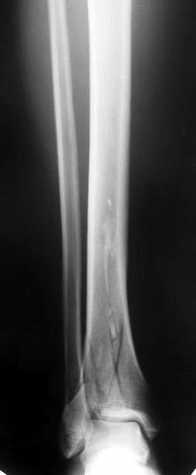

Уважаемые коллеги! Внутрисуставной перелом дистального конца б/б кости со смещением и подвывихом стопы должен был лечиться оперативно в раннем сроке.

Пример - довольно похожий перелом, оперированный в первые 8 часов после аварии у 40-летнего больного, страдающего тяжёлым сахарным диабетом 1 типа.